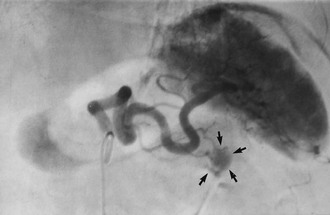

Primary sclerosing cholangitis (PSC) is a rare condition, probably of autoimmune origin, causing progressive fibrosis and multiple biliary strictures. Luminal narrowing causes gradual and progressive obstructive jaundice and, later, secondary cirrhosis. It may arise sporadically but often occurs in longstanding ulcerative colitis. Bile duct stenosis is usually diffuse, with a characteristic ERCP appearance (see Fig. 24.7), but just occasionally it is localised to the extrahepatic biliary system. Here the radiological appearance is indistinguishable from cholangiocarcinoma, causing a diagnostic predicament. Management is by endoscopic dilatation of clinically significant strictures and prescribing choleretic drugs to improve bile flow. In advanced cases, liver transplantation is an option; interestingly, up to a third demonstrate cholangiocarcinoma in the excised liver.